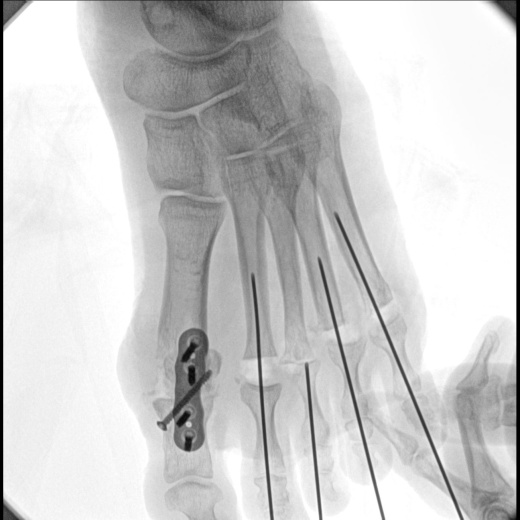

В качестве приемника используется динамический плоскопанельный детектор 26×26 см с разрешающей способностью более 4,5 пар.лин./мм., позволяющий визуализировать мельчайшие объекты с высоким разрешением. За счет применения динамического плоскопанельного детектора отсутствует эффект дисторсии, что повышает диагностическую значимость исследований. Большой диапазон выбора значений кадров с секунду при импульсной рентгеноскопии позволяет значительно снизить лучшею нагрузку, при этом при необходимости возможно проводить исследования с частотой до 30 кадров в секунду.

- Мобильный цифровой рентгенохирургический аппарат на базе штатива типа С-Дуга с цифровым плоско панельным детектором 26х26 см;